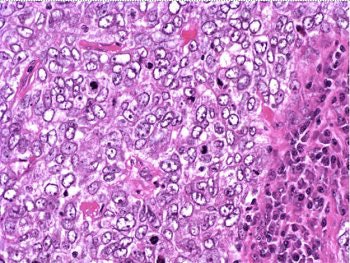

The patient underwent a lumpectomy with sentinel node biopsy. The pathology again showed extensive mitoses consistent with grade III invasive ductal carcinoma. Figure 4 (below) shows a representative microscopic section of the mass 4 cm from the nipple at a magnification factor of 100x. Figure 5 is the same area magnified 400x. Figure 6 shows a representative microscopic section from the other mass, which was 3 cm from the nipple magnified 100x. Figure 7 is magnified 400x. The tumors were estrogen receptor- and progesterone receptor-negative. Two sentinel nodes were negative.

Figure 4: Above, IDC right breast, 10 o'clock, 4 cm from the nipple magnified 100x. Figure 5: Below, IDC right breast, 10 o'clock, 4 cm from the nipple magnified 400x. |

Figure 6: Above, IDC right breast, 10 o'clock, 3 cm from the nipple magnified 100x. Figure 7: Below, IDC right breast, 10 o'clock, 3 cm from the nipple magnified 400x. |